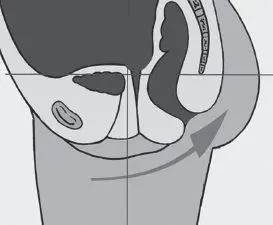

Рис. 1. Нормальное положение таза

Рис. 2. Нормальное положение таза

В норме гравитационная вертикаль проходит через промежность и отверстие большого Родничка (Рис. 2).

Именно такое положение обеспечивает нормальное состояние лобково-копчиковой мышцы, которая простирается от лобковой кости до копчика, поддерживает анус и остальные граничащие с ним внутренние органы, не давая им опуститься. Находится она на расстоянии 2–3 см от кожного покрова. Мышца управляется нервом, который контролирует активность ануса и половых органов, посылая сигналы от них в мозг и передавая их обратно.

Лобково-копчиковая мышца также связана с тазовым внутренним нервом, ответвление которого у женщин соединяет нижнюю часть позвоночника с маткой и мочевым пузырем, ау мужчин – с простатой и мочевым пузырем. Соответственно, правильное положение костей таза гарантирует здоровый физиологический тонус мышцам тазового дна, что обеспечивает здоровье урогенитальной системы человека.

Все отклонения в положении таза: высокое или низкое положение копчика, смещение лобковой кости в результате травм и пр. (Рис. 3–4), перерастягивают мышцы тазового дна, либо, напротив, лишают их опоры, в результате чего они провисают растянутым гамаком. Эти отклонения фасциально передаются по телу, заставляя его искажаться и искать пути компенсации для сохранения вертикального положения.